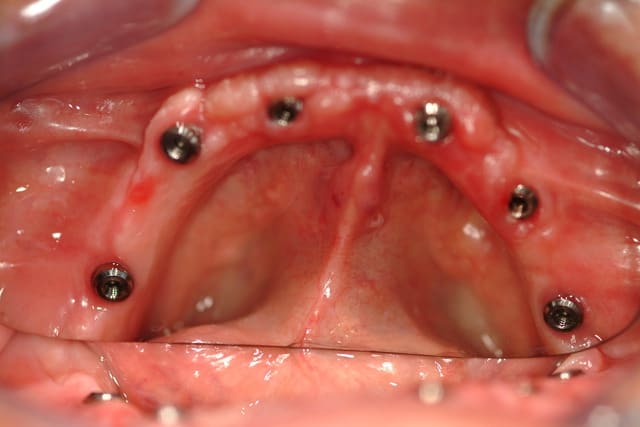

J'ai abandonné la MCI au maxillaire sur 4 implants c'est trop risqué.

Aucun filet de secours, je préfère avoir au moins 6 implants bloqués à min 30 Ncm, pour mettre en charge un maxillaire complet.

A la mandibule 4 implants, ça fonctionne très bien, j'en ai fait beaucoup aussi.

Voici déjà un cas avec 6 implants maxillaire et mandibulaire.

Le bas est pour le moment en résine, on doit passer plus tard à un bridge vissé sur armature métallique.